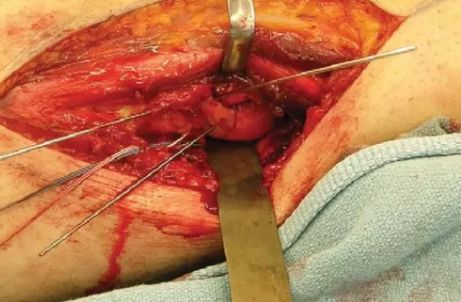

骨与软组织并重:Hoffa骨折往往也伴有肌腱、韧带附着点的损伤,故对这些组织结构的解剖复位对恢复膝关节的稳定性和功能也至关重要。

(Hoffa合并PCL损伤一期修复)